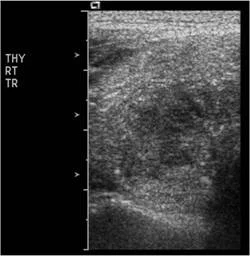

【108-1 醫學(三) 第74題】

⼀位女性病患右側甲狀腺及右下邊脖⼦淋巴腺無痛性腫⼤,其右側甲狀腺灰階及彩⾊杜⼘勒超⾳波檢查如圖,最可能的診斷為何?

這題的解題核心在於辨識甲狀腺超音波影像中惡性結節的典型特徵,特別是微鈣化點和豐富的內部血流,這些都強烈指向甲狀腺乳突狀癌。